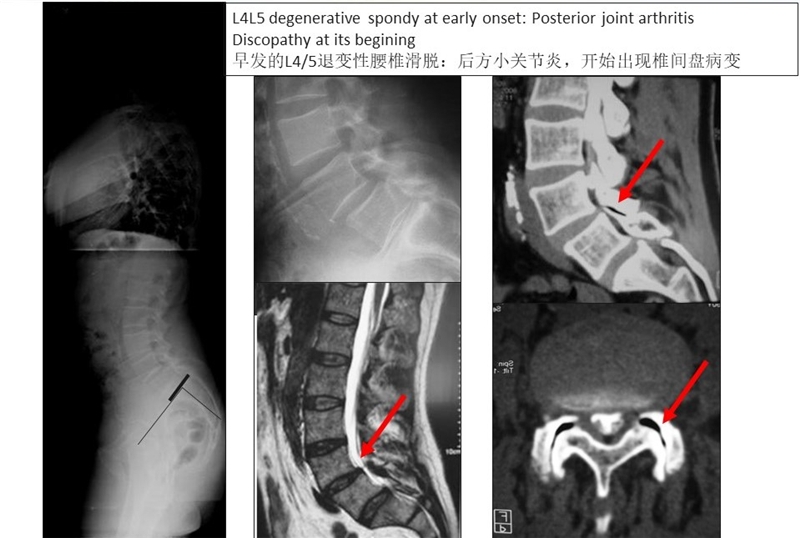

在腰椎前凸较小的1型和2型人群中,腰椎接触应力主要集中于前柱和中柱,此类人群更易出现早期椎间盘退变;而在腰椎前凸较大的4型人群中,腰椎应力主要集中于后柱,此类人群腰椎小关节和峡部应力负荷较大,易出现小关节增生、腰椎滑脱和侧方滑移。

4型人群易出现小关节增生、腰椎滑脱和侧方滑移